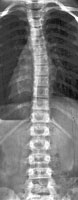

Возможность использования топографического мониторинга состояния больных сколиозом взамен рентгена была изучена на основе клинического материала школы-интерната №133 для детей больных сколиозом г.Новосибирска, где, начиная с 1995 года, проводились ежегодные обследования на ТОДП постоянного контингента больных параллельно с рентгеном. Среди больных по характеру течения заболевания выделены 3 группы: СФ - стабильная форма сколиоза, УПФ - умеренно прогрессирующая, БПФ - быстро прогрессирующая форма. Пример наблюдения больной с быстро прогрессирующей формой сколиоза приведен на рисунках ниже.

9,0 лет 10,4 лет 10,8 лет 11,4 лет 12 лет

PTI=1,0; Cobb=10° PTI=1,3; Cobb=17° PTI=1,9; Cobb=23° PTI=2,9; Cobb=38° PTI=3,6; Cobb=55°

За трехлетний период наблюдения в возрасте с 9 до 12 лет основная правосторонняя грудная дуга по углу Кобба спрогрессировала с 10 до 55°, т.е. средняя скорость прогрессирования составила 15° в год. Общий индекс нарушения формы дорсальной поверхности туловища PTI изменился с 1,0 (граница нормы и умеренно выраженных отклонений) до 3,6 (значительное отклонение). Следует обратить внимание, что в начале наблюдения туловище больной имело хороший баланс во фронтальной плоскости (вертикальная ось, проходящая через вершину межъягодичной складки, проходит также и через C7), а с возраста 10,8 лет стало явно нарастать нарушение баланса с отклонением туловища вправо, т.е. в сторону выпуклости основной дуги. Приведенный пример убедительно демонстрирует наглядность топографических данных и их большую информативность для решения задачи неинвазивного мониторинга состояния больных сколиозом.